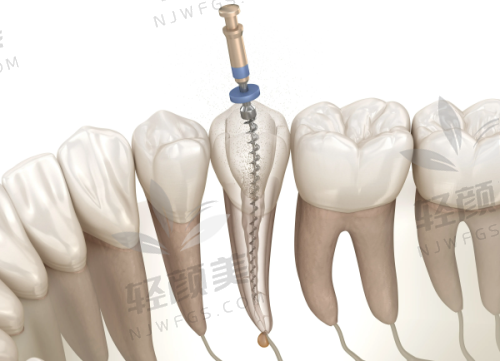

根管治疗的核心目的是清除感染的牙髓组织,防止进一步扩散,保住牙根结构——这是让你牙齿“假死而不拔”的高阶“急救操作”!

根管治疗什么时候做更合适?讲真,有几个明显信号一出现,就别再等了:

✔️ 龋齿越过界线 → 龋坏深入牙髓,牙神经都吓冒烟,不处理分分钟发展成根尖周炎。

✔️ 牙齿变色(灰黑/暗黄) → 特别可能牙髓已经坏死,继续放任等于是“僵尸牙”挂号排队。

✔️ 外力撞击 → 就算牙齿表面没崩,也可能内部已经髓腔受伤,早做检查,早发现、早处理。

✔️ 牙龈反复长包流脓 → 根尖囊肿的预警信号之一,别靠吃几颗消炎药糊弄过去!

✔️ 冷热刺激已久 → 牙神经已经持续受伤敏感,这是牙髓的“求救短信”!